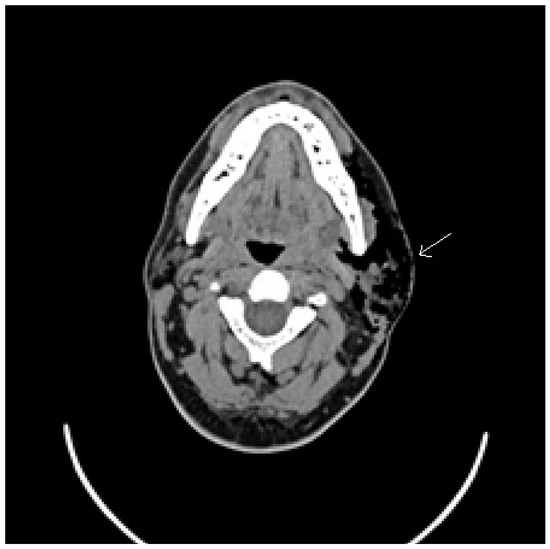

- Krief, O.; Gomori, J.M.; Gay, I. CT of pneumoparotitis. Comput. Med Imaging Graph. 1992, 16, 39–41. [Google Scholar] [CrossRef]

- Golz, A.; Joachims, H.Z.; Netzer, A.; Westerman, S.T.; Gilbert, L.M. Pneumoparotitis: Diagnosis by computed tomography. Am. J. Otolaryngol. 1999, 20, 68–71. [Google Scholar] [CrossRef]

- Apaydin, M.; Sarsilmaz, A.; Calli, C.; Erdogan, N.; Varer, M.; Uluç, E. Giant pneumoparotitis. Eur. J. Radiol. Extra 2004, 52, 17–20. [Google Scholar] [CrossRef]

- Lasboo, A.A.; Nemeth, A.; Russell, E.J.; Siegel, G.J.; Karagianis, A. The use of the “puffed-cheek” computed tomography technique to confirm the diagnosis of pneumoparotitis. Laryngoscope 2010, 120, 967–969. [Google Scholar] [CrossRef]